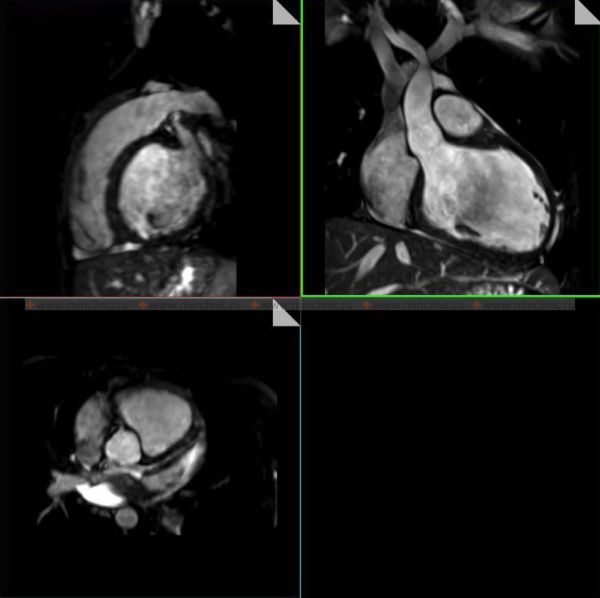

МРТ (магнитно-резонансная томография) органов грудной клетки — это способ визуализации с применением силового магнита и радиоволн, с помощью которых в дальнейшем строится изображение органов грудной клетки (сосуды, сердце, лёгкие). Во время проведения МРТ (магнитно-резонансной томографии) органов грудной клетки 3,0 Т (тесла) пациент не получает радиационного облучения (лучевой нагрузки).

МРТ (магнитно-резонансная томография) грудной клетки позволяет специалистам получить изображение расположенных там органов пациента (сердце, бронхи, лёгкие и т.д.) для оценки их функционального состояния или выявить произошедшие в них органические изменения.

- оценка органов грудной клетки в трёхмерной реконструкции под разными углами;